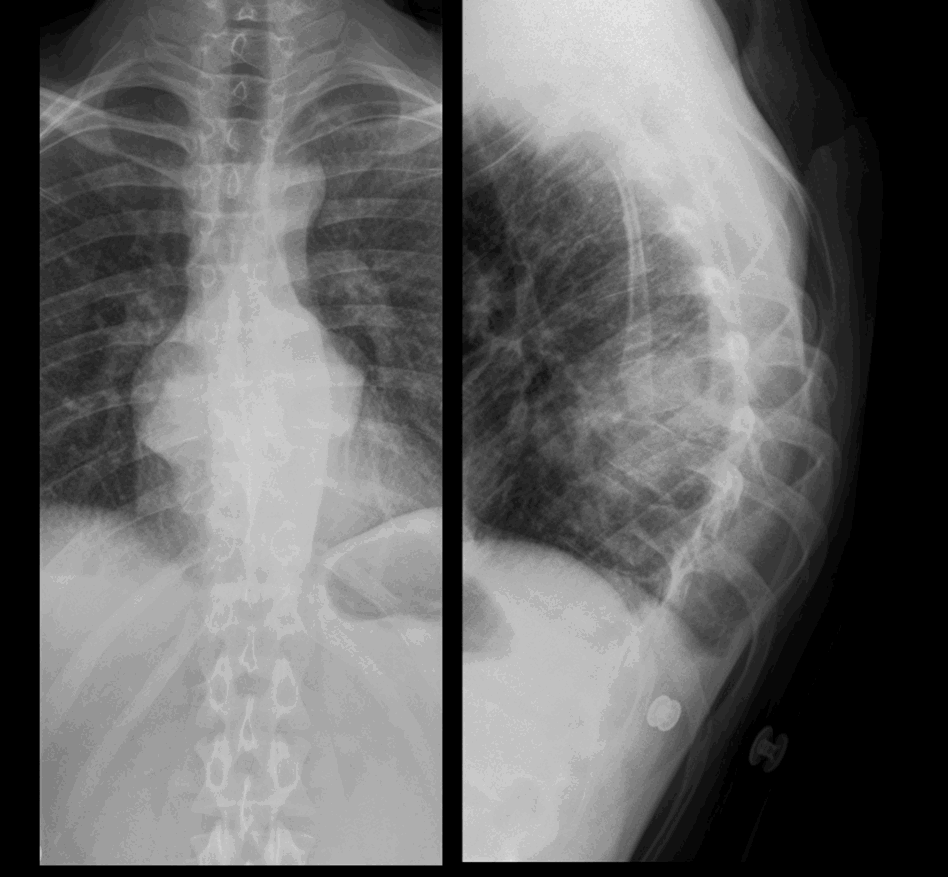

Age 24 male. Referral from GP. History: increasing back pain

Examiner marking guidance

Findings:

Bilateral posterior/retrocardiac paraspinal soft tissue

Acute kyphosis, with almost complete collapse of mid thoracic vertebral body (T8) with anterior wedging

Lungs clear, blunting of one posterior costophrenic recesses on lateral view that may be due to small pleural effusion

Likely diagnosis spinal tuberculosis (TB) with paraspinal abscess

Unlikely to be malignancy

Management:

Urgent MRI/spinal referral/TB referral

| Sample answer | Answer type | Explanation of scoring allocation |

|

Bilateral paravertebral stripe widening at T8 with collapse of T8 vertebral body and kyphosis. Urgent MRI whole spine with contrast. Inform referrer urgently. Antibiotics. Microbiology. Drainage. |

High scoring answer |

This answer would score highly because it is accurate and concise with appropriate suggestions for further imaging and management. |

Soft tissue mass in the posterior mediastinum causing complete collapse and destruction of a mid-thoracic vertebra and focal kyphosis, this is concerning for spondylodiscitis Compare to previous CXR, email GP the report, advise urgent MRI spine for further evaluation |

Mid scoring answer |

This answer would not score so highly because it is less anatomically detailed (the precise vertebral body is not specified) and a potential causative organism is not mentioned. |

-Paravertebral soft tissue densities projected in the retrocardiac region bilaterally. This corresponds with density projected over vertebral bodies on the lateral projection Imp: Paravertebral masses - likely neurogenic e.g. Neurofibroma, schwannoma MRI Thorax is advised. |

Low scoring answer |

This answer is low scoring as neither the T8 vertebral body collapse nor the kyphosis is mentioned. The list of differential diagnoses provided is for a posterior mediastinal mass without recognising that the pathology in this case is centred on the spine. |